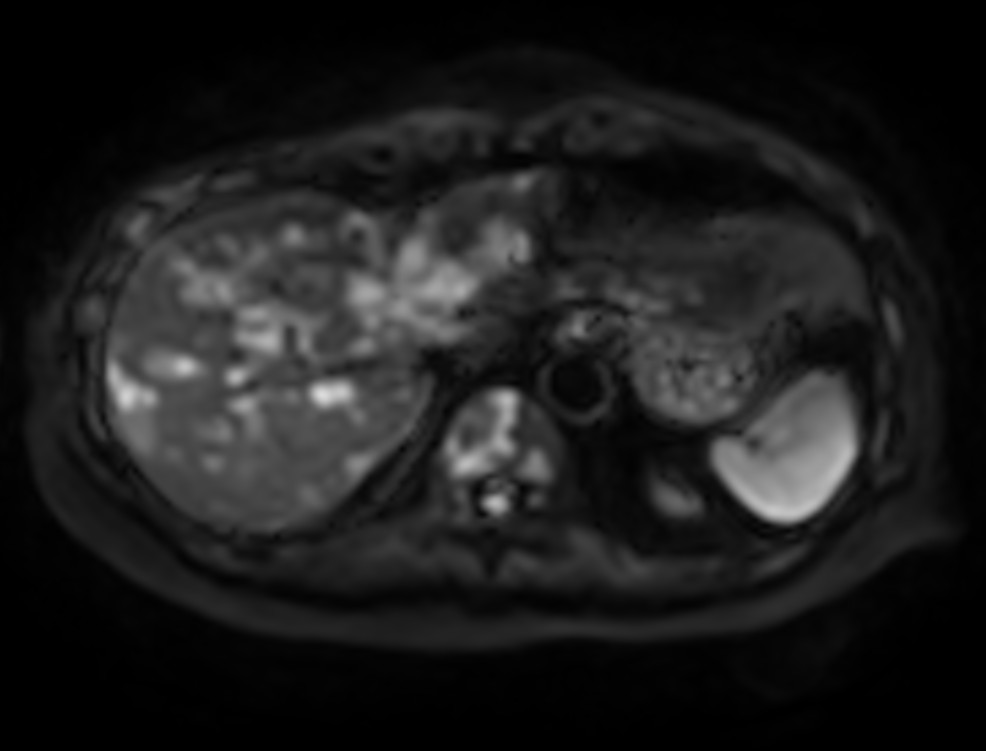

Liver metastasis with SmartSpeed Precise

Axial DWI b200

Axial DWI b800

Axial DWI ADC